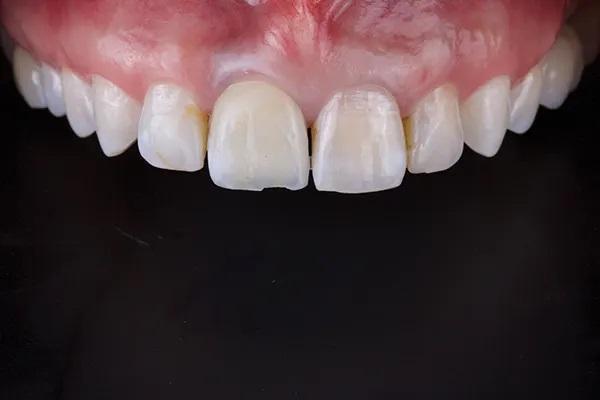

После примерки внутренние поверхности реставраций были протравлены плавиковой кислотой в течение 20 секунд и силанированы в соответствии с инструкциями производителя, а поверхности опор из диоксида циркония были обработаны воздушно-дисперсионной обработкой и специальной керамической грунтовкой в соответствии с APC (воздушно-абразивная обработка, грунтовка с MDP, цемент из композитной смолы) технология склеивания с диоксидом циркония. Была выполнена адгезионная цементировка по протоколу фиксации на полимерный цемент двойного отверждения, стойкого к изменению цвета и имеющего четкий оттенок (Фото 14 – Фото 18).

Фото 14. Вид окончательных реставраций в полости рта, после фиксации.